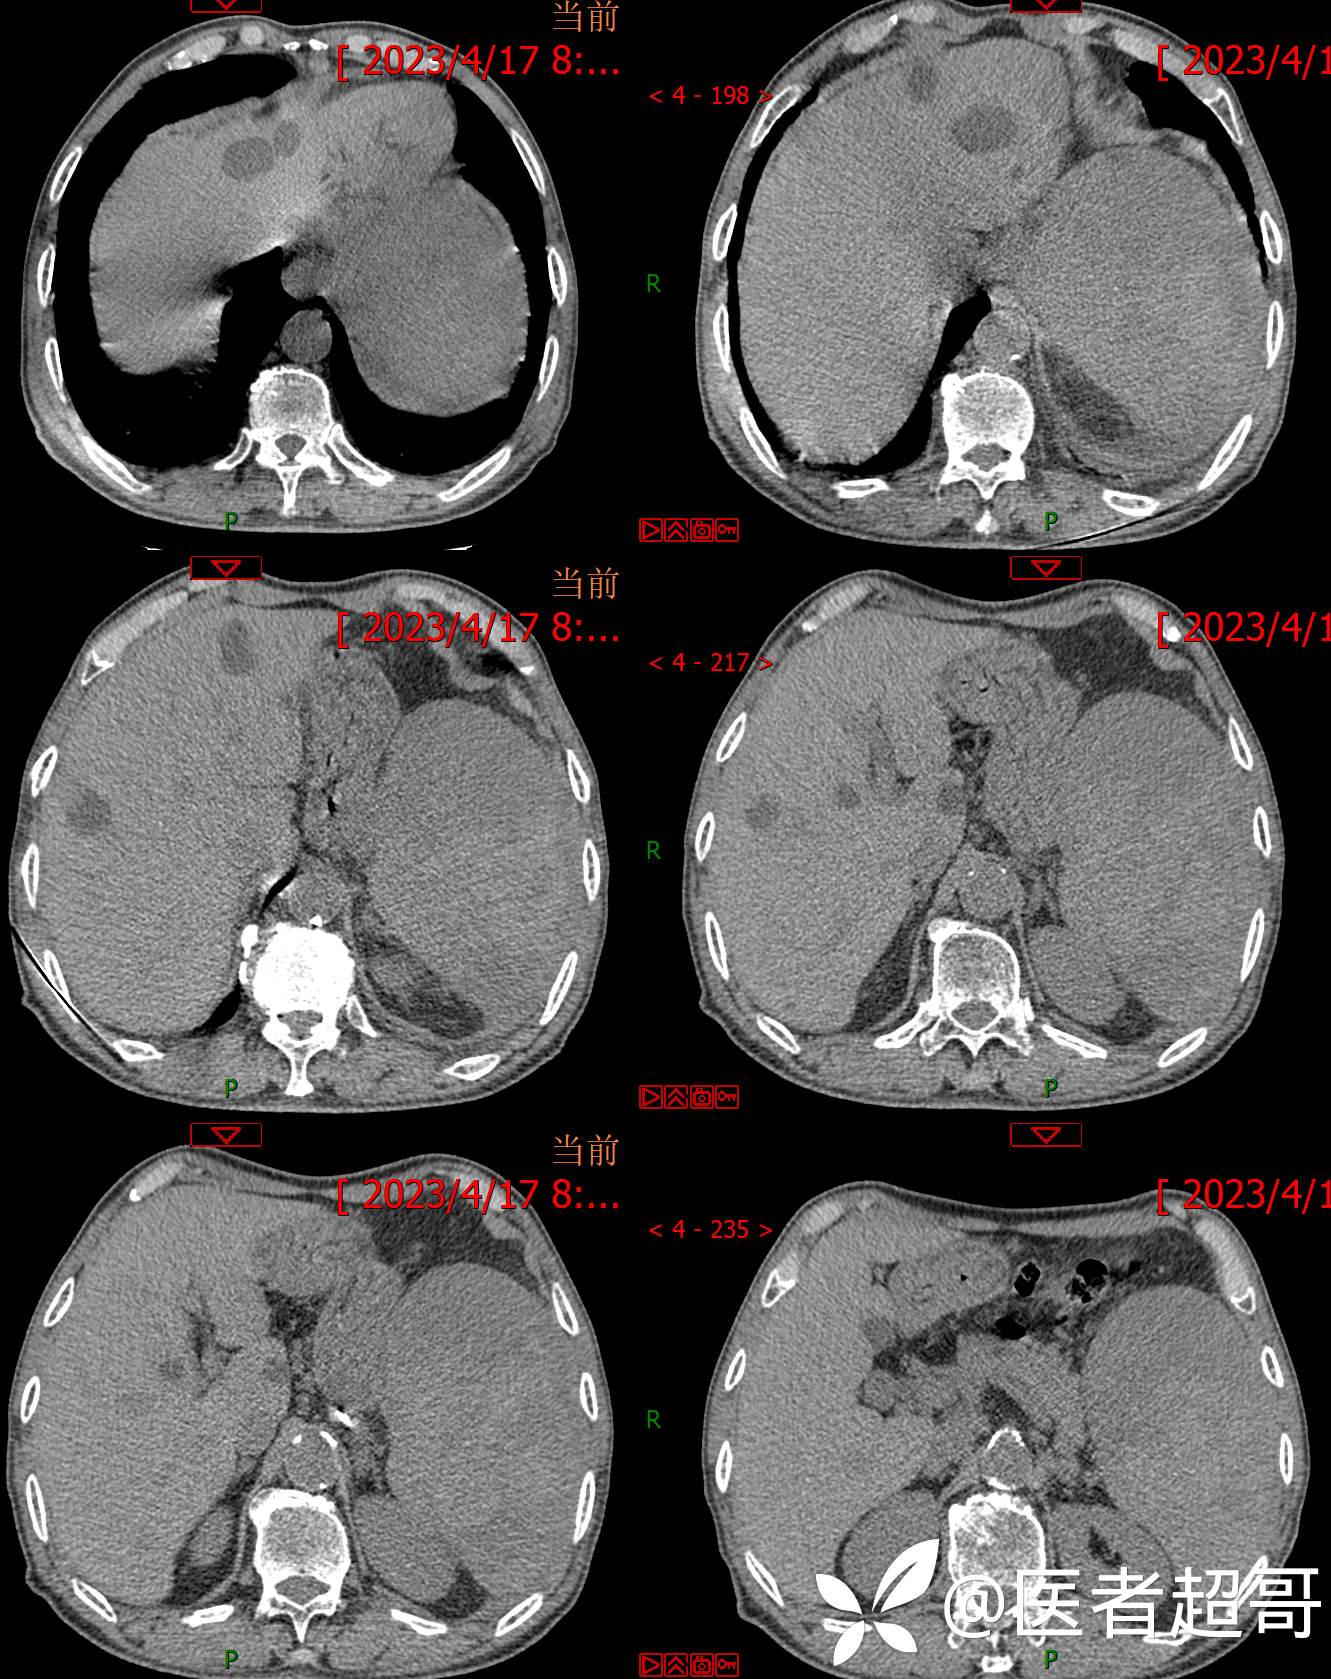

一波三折,术前确诊,术后肝脏广泛爆发,原因在何?让我们一探究竟!欢迎留言分析~~~

简要病史:左侧胸部疼痛不适5天就诊,临床初步诊断“肋软骨炎”。

术后三个月复查CT、MRI表现:

两次穿刺显示阴性。